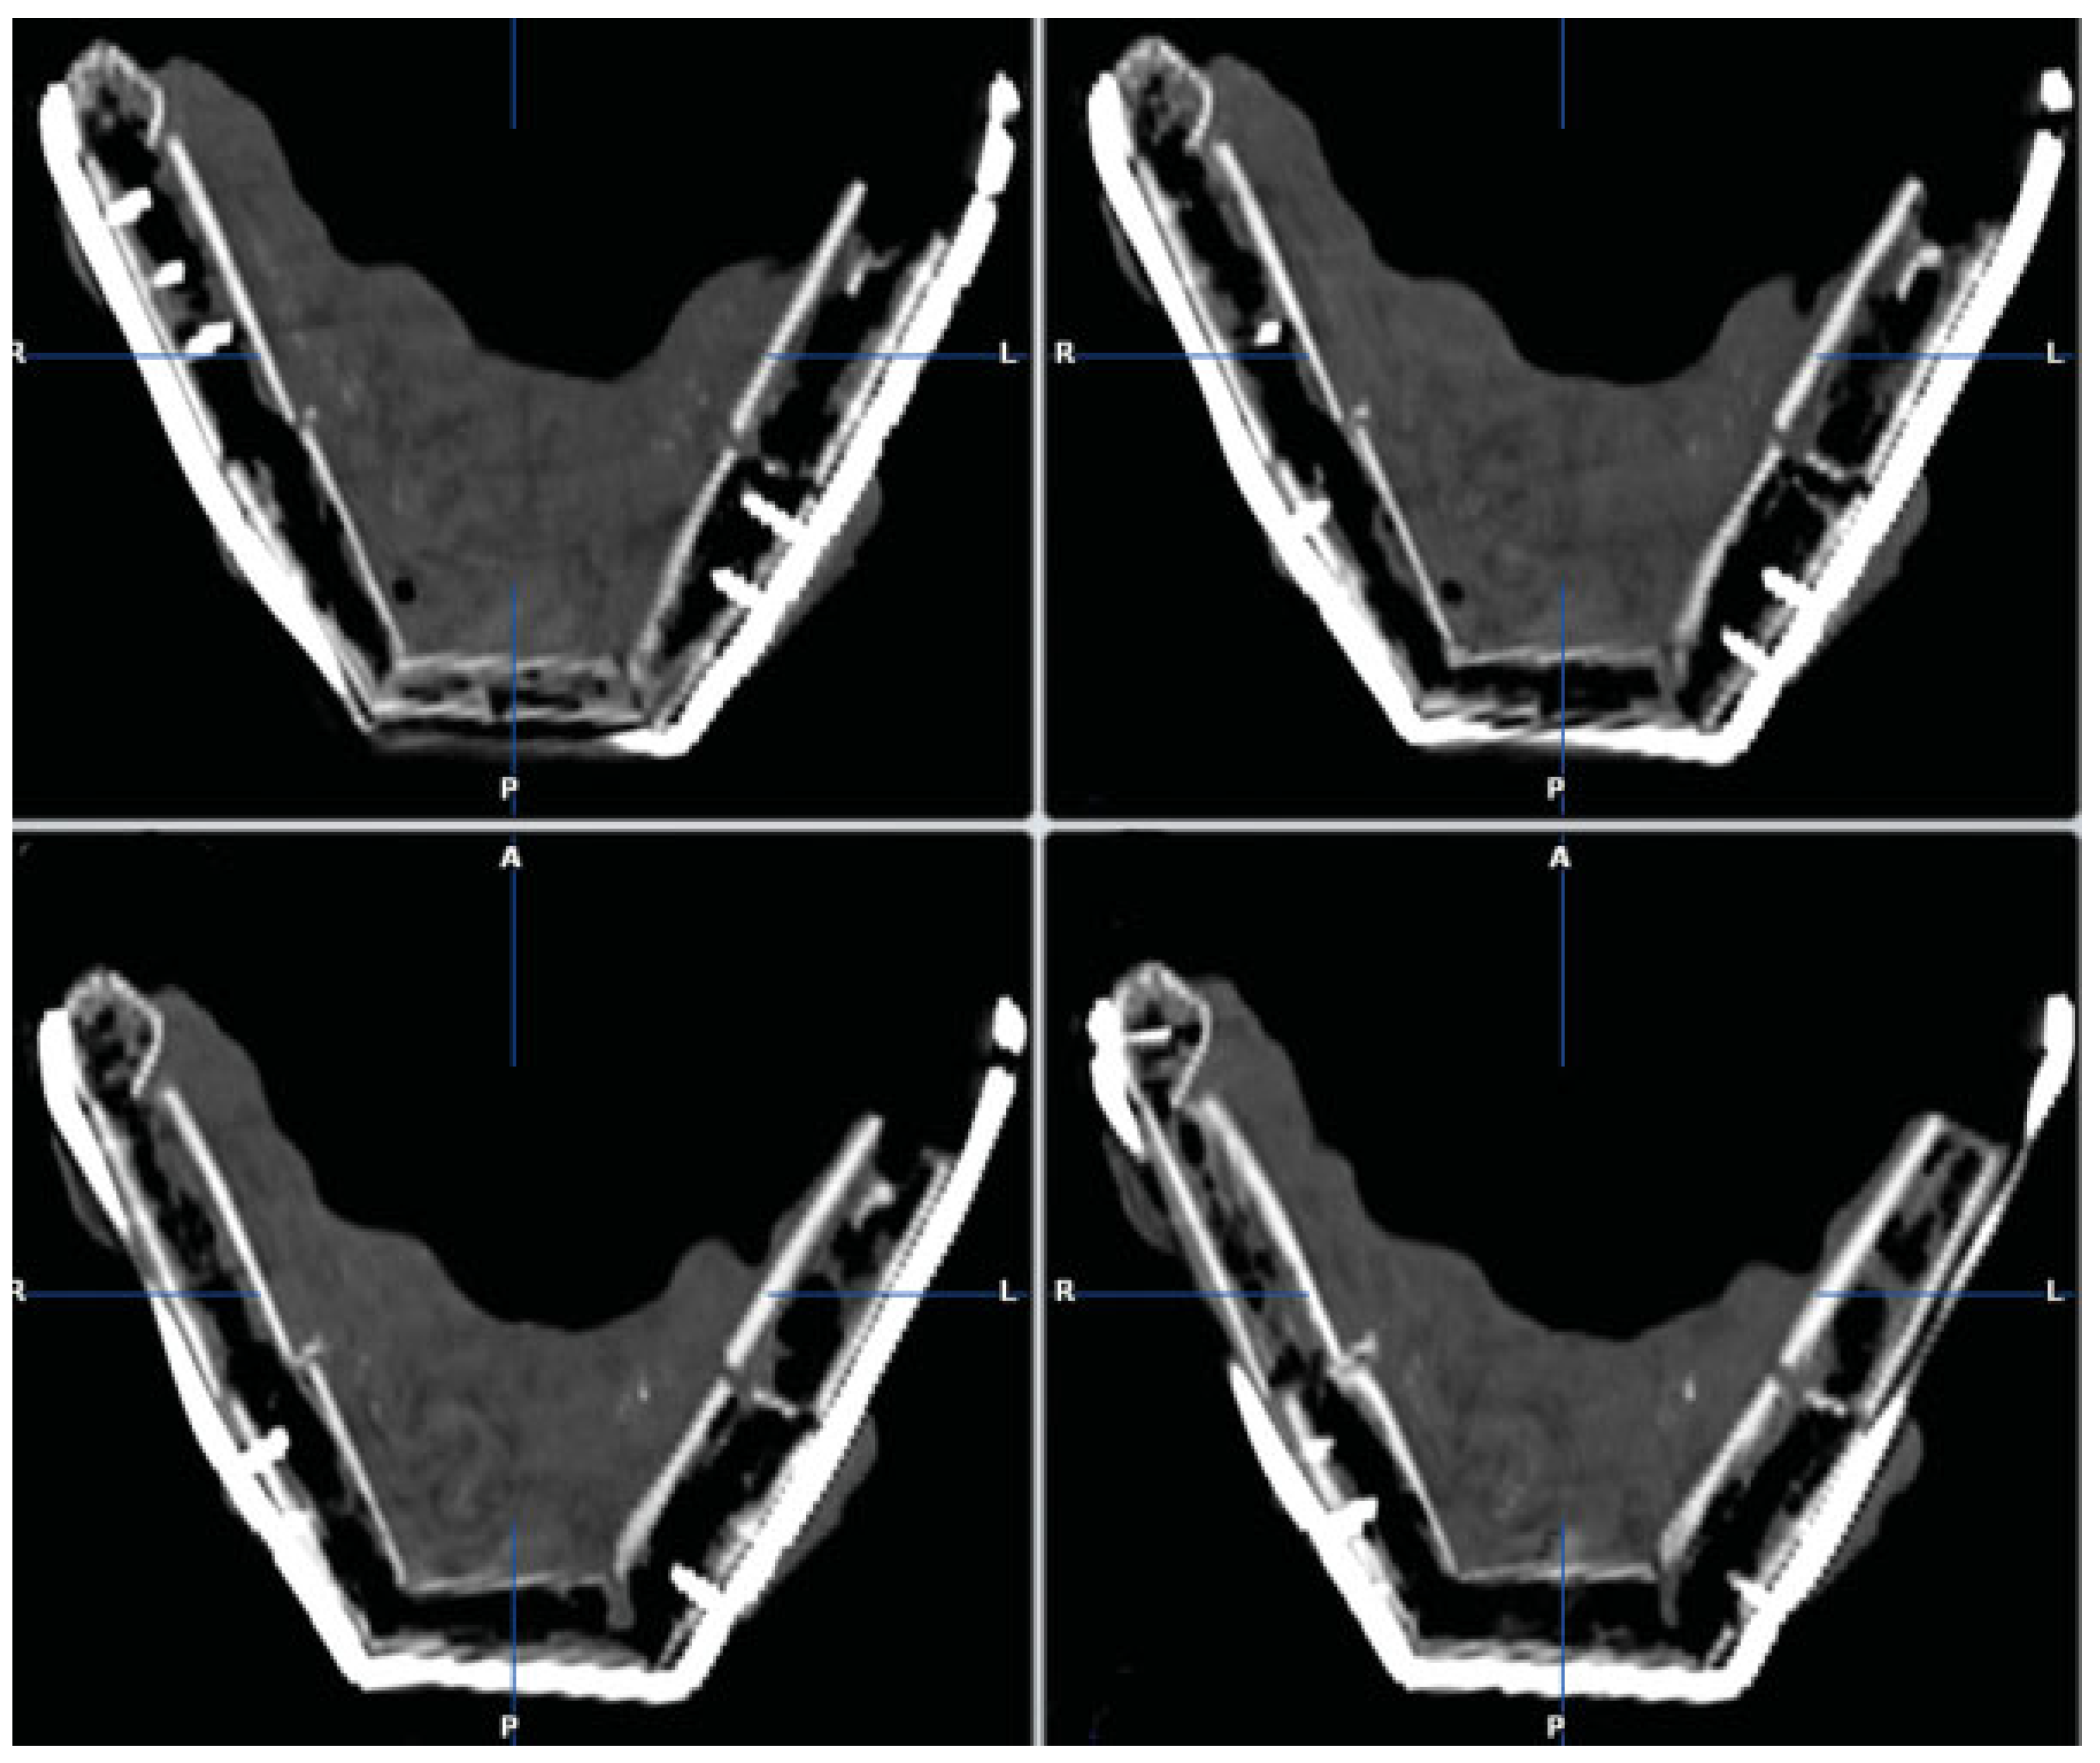

The fusion of preoperative and postoperative CT datasets showed that the positions of the two residual rami and condyles after the fixation of the CAD/CAM-fabricated reconstruction plate were almost identical to those before resection (Figure 10). We were thus able to transfer the virtually planned position of the patient-specific CAD/CAM-fabricated reconstruction plate precisely to the site of surgery. Accordingly, there was no dislocation of the residual bone segments (both rami and condyles).

Figure 10. The fusion of preoperative (amber) and postoperative (blue) CT datasets demonstrated that the positions of the two residual rami and condyles after the fixation of the CAD/CAM-fabricated reconstruction plate were almost identical to those before resection. (A) Axial view. (B) Coronal view.